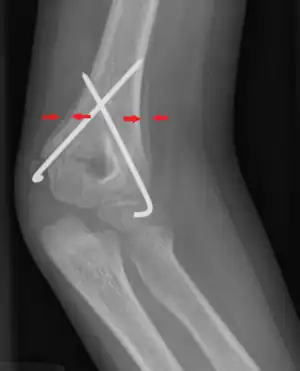

| Periosteal reaction on a healing supracondylar fracture | |

A periosteal reaction is the formation of new bone in response to injury or other stimuli of the periosteum surrounding the bone.[1] It is most often identified on X-ray films of the bones.